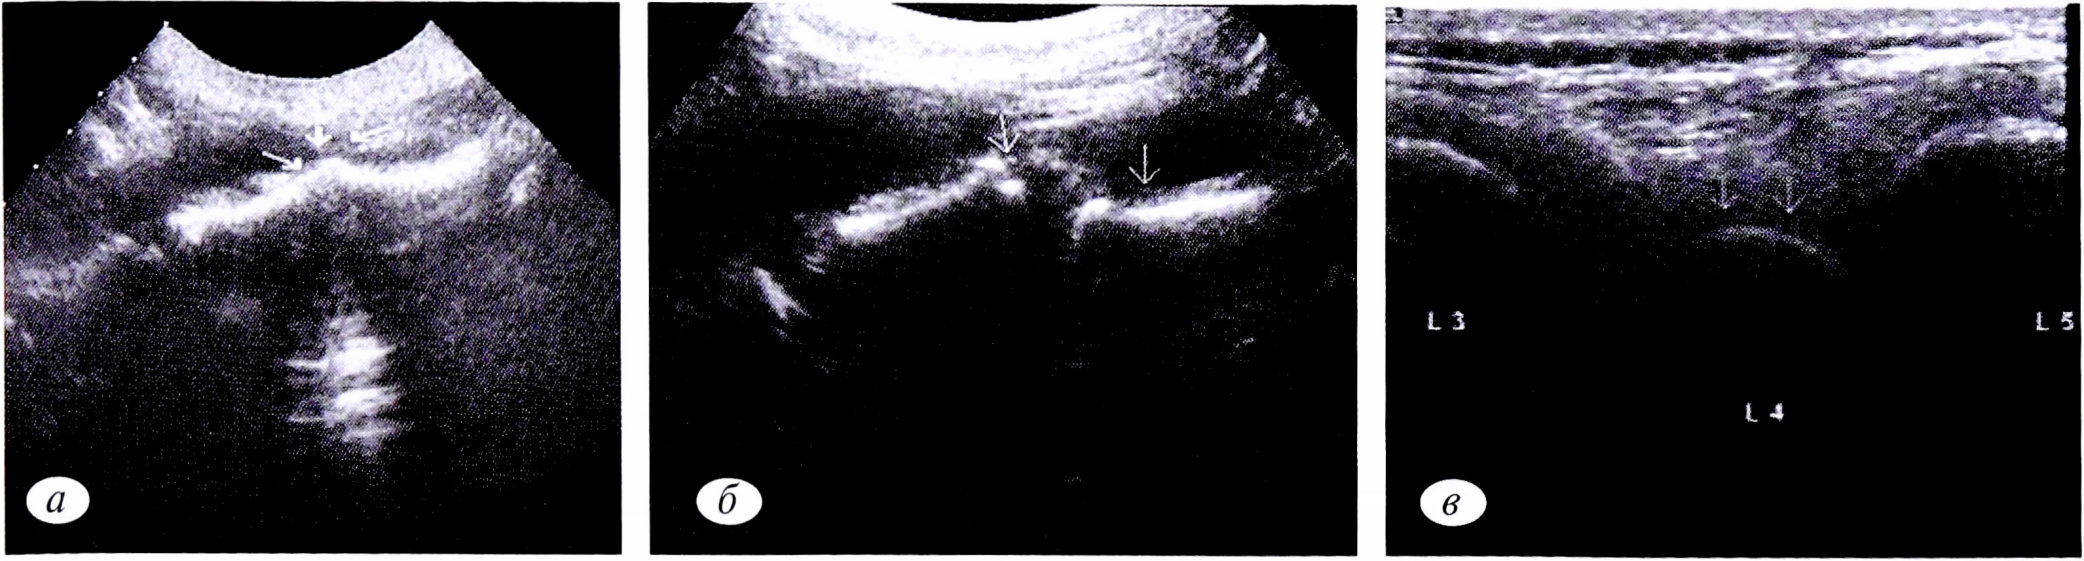

Ультрасонография из переднего и заднего доступов выполнена в 35 наблюдениях. Признаками нестабильности позвоночного сегмента являются смещение передних границ межпозвонковых дисков, ступенеобразное смещение переднего контура тел позвонков, смещение задних контуров остистых отростков при функциональных пробах (рис. 6).

Рис. 6. Эхограммы при различных степенях нестабильности позвоночного сегмента. а — смещение передних границ межпозвонковых дисков; б — ступенеобразное смещение переднего контура тел позвонков; в — смещение задней границы остистого отростка смещенного кпереди позвонка.

Fig. 6. Echograms at different degrees of instability of the vertebral segment. a — displacement of the anterior boundaries of the intervertebral discs; b — stepwise displacement of the anterior contour of the vertebral bodies; c — displacement of the posterior border of the spinous process of the displaced anterior vertebra.

Кровоток в области позвоночного двигательного сегмента также менялся в зависимости от выраженности нестабильности. Вначале, когда имело место только пролабирование переднего отдела диска, он был не изменен. При выраженной нестабильности визуализировалось усиление кровотока с появлением новообразованных сосудов, врастающих в диск [5].